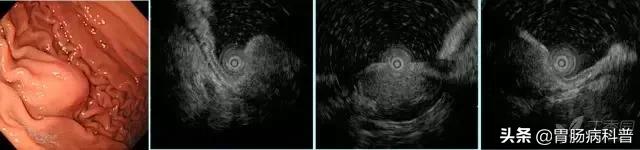

图4 异位胰腺(浅型)。

白光胃角可见脐样黏膜下隆起,超声内镜下可见黏膜肌层-黏膜下层有一界线不清之偏高回声病变

图5 胃体异位胰腺(深型)。

白光下胃体大弯可见半球型黏膜下隆起,超声内镜下可见一界线模糊的偏高回声病变,起源于黏膜下—固有肌层,类似肌层增厚表现